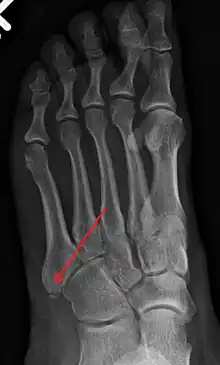

臨床意義